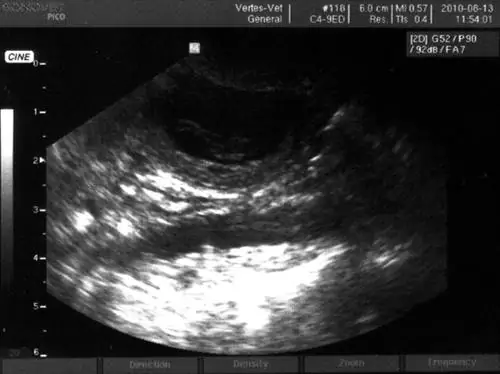

С плодом и так все в порядке, его отец провожал меня на обследование, а потом я показываю ему в коридоре распечатанное фото УЗИ:

Это изображение предназначено только для иллюстрации. До

- А вот смотрите, вот его голова, а это ноги.

Какой он:

- Если бы вы сейчас поставили передо мной эту картинку, что мы не можем приземлиться на самолете в Варшаве из-за тумана, я бы легко в это поверил.